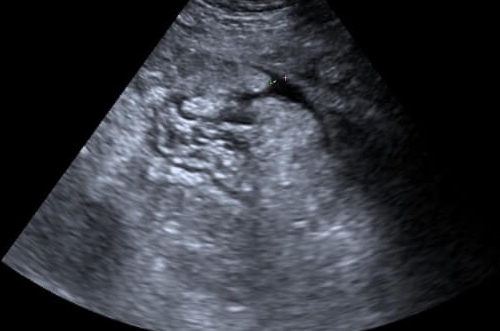

卵巢过度刺激综合征是促排卵治疗后常见的并发症,主要是由于促排卵药物刺激卵巢,导致多个卵泡同时发育,体内雌激素水平过高,引发卵巢增大、血管通透性增加等一系列病理生理改变。轻症OHSS患者通常仅表现为轻度腹胀、腹痛,卵巢轻度增大,血液生化指标基本正常。这种情况下,患者的身体状况相对稳定,对胚胎移植的影响较小。

对于中重度OHSS患者,情况则更为复杂。此时卵巢明显增大,伴有腹水、胸水,血液浓缩、电解质紊乱等严重症状,身体处于应激状态,子宫内环境也会受到较大影响,通常不建议立即进行胚胎移植。